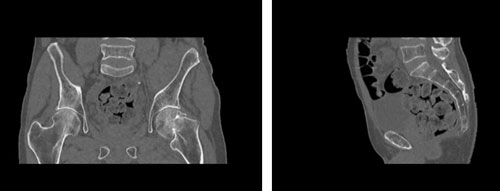

WEK54-01股骨頸骨折骨盆模型,WEK54-01骨盆模體詳細(xì)介紹:

WEK54-01股骨頸骨折骨盆模型,WEK54-01骨盆模體模擬沒有靜脈造影劑的骨盆(天然)。它覆蓋了整個(gè)骨盆,直到第五腰椎。

左側(cè)股骨頸移位骨折。

該模型可用于 CT(包括 CBCT)和射線照相,以評(píng)估和優(yōu)化成像性能和后處理應(yīng)用,包括支持 AI 的應(yīng)用。它也適用于培訓(xùn)目的。

WEK54-01股骨頸骨折骨盆模型,WEK54-01骨盆模體成像效果圖:

SAG: